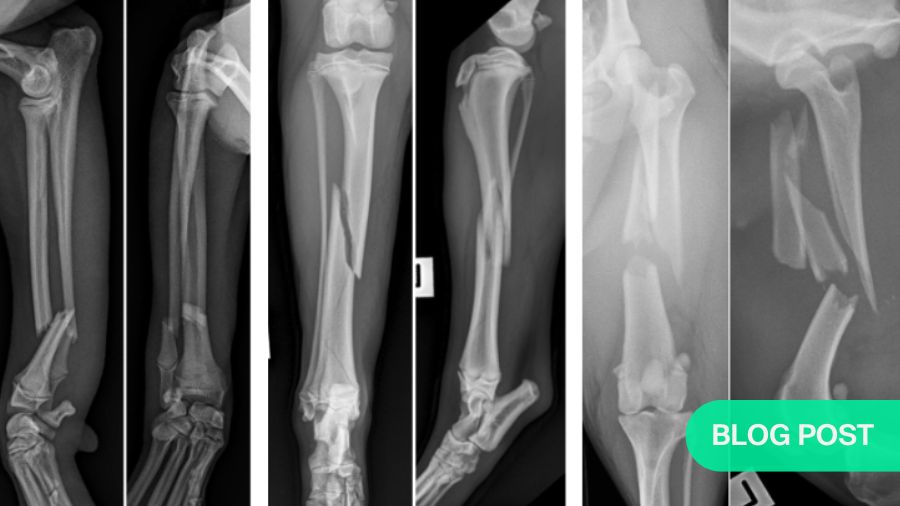

Which fractures should be reconstructed?

Examine your radiographs to determine contraindicated and indicated repair options

For simple fractures, anatomic reconstruction is normally indicated

Most importantly for fixation decisions, X-rays show how many bone fragments there are. If there are only two (a simple fracture), anatomic reconstruction is normally indicated. However, be sure to look closely for fissures in the bone, as these may indicate or lead to comminution and will weaken the bone.

Four-piece (comminuted) fractures: anatomic reconstruction is not an option

Three-piece injuries: the grey zone